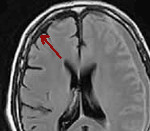

Наиболее информативны КТ головного мозга с контрастированием и МРТ. На КТ субдуральная эмпиема видна как серповидная полоса под сводом черепа, над которой после введения контраста возникает узкая полоска повышенного сигнала. Однако при малом размере эмпиемы КТ может давать ложноотрицательный результат. МРТ головного мозга позволяет не только выявить субдуральную эмпиему даже малых размеров, но и оценить ее размер и распространенность. По интенсивности МР-сигнала рентгенолог может дифференцировать эмпиему от серозного экссудата, хронической субдуральной гематомы и эпидурального абсцесса.